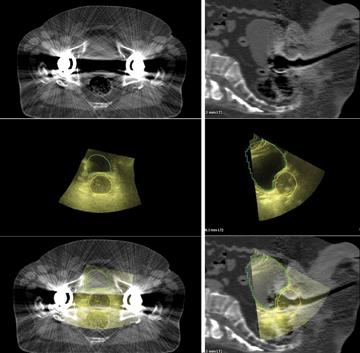

Axial (left column) and sagittal (right column) images of a patient with bilateral hip prostheses. Top images (Figure 1) are 3-D CT, middle (Figure 2) are Clarity 3-D ultrasound images with the prostate and bladder contoured, and bottom images are the fused 3-D datasets.

The transperineal approach puts the probe closer to the gland than other ultrasound techniques, does not depend on bladder filling and enables its use during standard intensity-modulated radiotherapy (IMRT)/volumetric modulated arc therapy (VMAT) approaches. The new TPUS images are typically clear, the external contours easily visible and continuous scanning allows for automated segmentation techniques that will facilitate concurrent treatment and imaging (Figure 2).